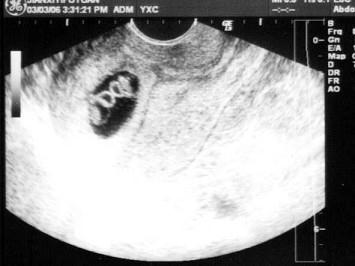

女,25岁,停经50天,B超检查如图所示,最可能的诊断为?(?)A.早孕(单胎)B.早孕(双胎)C.葡萄胎D.宫腔积血E.以上都不是

问题 女,25岁,停经50天,B超检查如图所示,最可能的诊断为?(?)

选项 A.早孕(单胎) B.早孕(双胎) C.葡萄胎 D.宫腔积血 E.以上都不是

答案 B